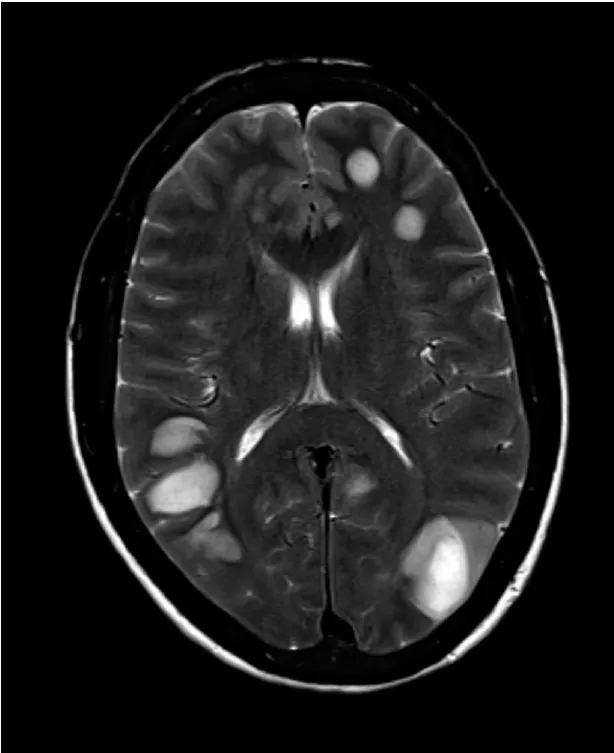

No entanto, não foi evidenciado melhora clínica com cobertura antibiótica, e para afastar possibilidade de

outra doença infecciosa, autoimune ou neoplasia foi realizada biópsia cerebral (Figura 2). Foi evidenciado PCR positivo para Nocardia no tecido cerebral, estabelecido o diagnóstico e iniciado tratamento com Cotrimoxazol+imipenem e observado melhora clínica e radiológica.

No seguimento clínico, após 2 meses de redução da imunossupressão foram identificados anticorpos anti-HLA

específicos contra o doador (DAS), realizado biópsia renal sendo evidenciada recorrência da NIgA com crescentes e provável rejeição humoral ativa.